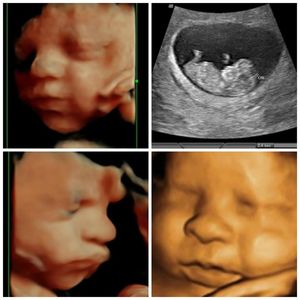

The clarity of Silhouette Imaging!

Our ultrasound equipment is the state of the art GE Voluson E10 with Silhouette Imaging. This machine is the best 2D/3D/4D/HD Live ultrasound machine available. The E10 allows the images to demonstrate extraordinary image quality from the first to the third trimester. GE continues to lead the industry’s technological advances and our equipment is regularly updated to give you access to the most advanced technology available, this providing images with amazing clarity and seeing your baby in motion.

Traditional 2D imaging uses sound waves to produce the familiar black and white image of your

baby. In 3D and 4D and HD Live, light waves add an extra dimension to give a better view of baby's face

and features. Our technology provides unrivaled imaging so you can clearly see your little

one in real time. You will be amazed by how fast your baby is growing and developing!